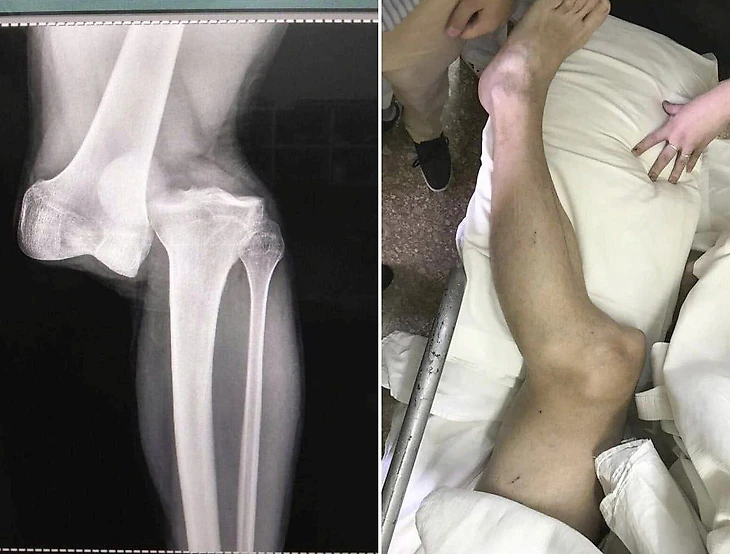

На прошлой неделе в матче 1/8 Кубка Либертадорес между «Флуминенсе» и «Аргентинос Хуниорс», Марсело получил прямую красную карточку за фол на 29-летнем аргентинце Лусиано Санчесе (предупреждаем, что кадры шокирующие).

А теперь в сети появились снимок и фото поврежденной ноги.